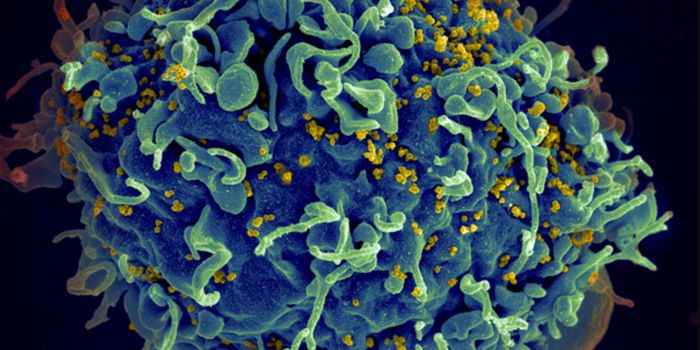

MAY 23, 2024MicrobiologyWhen human immunodeficiency virus (HIV) emerged and was identified as the cause of acquired immunodeficiency syndrome (A ...